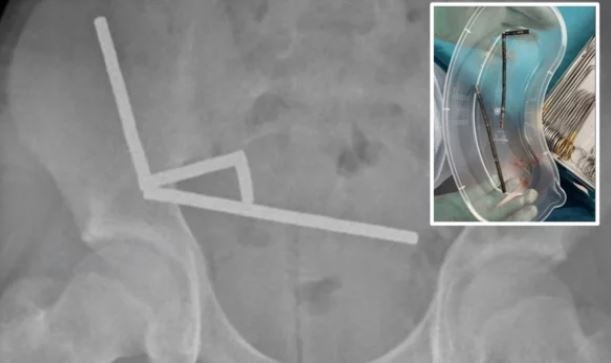

Fotot me rreze X zbuluan katër vargje magnete të shpërndara në pjesë të ndryshme të zorrëve të djaloshit. Pasi futën në sistemin tretës, pjesët e vogla metalike u lidhën ndërmjet tyre.

Gjatë operacionit u vërtetua që vargjet e magnete nga zorra e hollë dhe nga zorra e verbër ishin tërhequr pranë njëri-tjetrit, duke shtypur inde të mesme.

Kjo çoi në ndërprerjen e furnizimit me gjak dhe vdekjen e disa pjesëve të zorrëve – gjendje e njohur si nekrozë si pasojë e presionit.